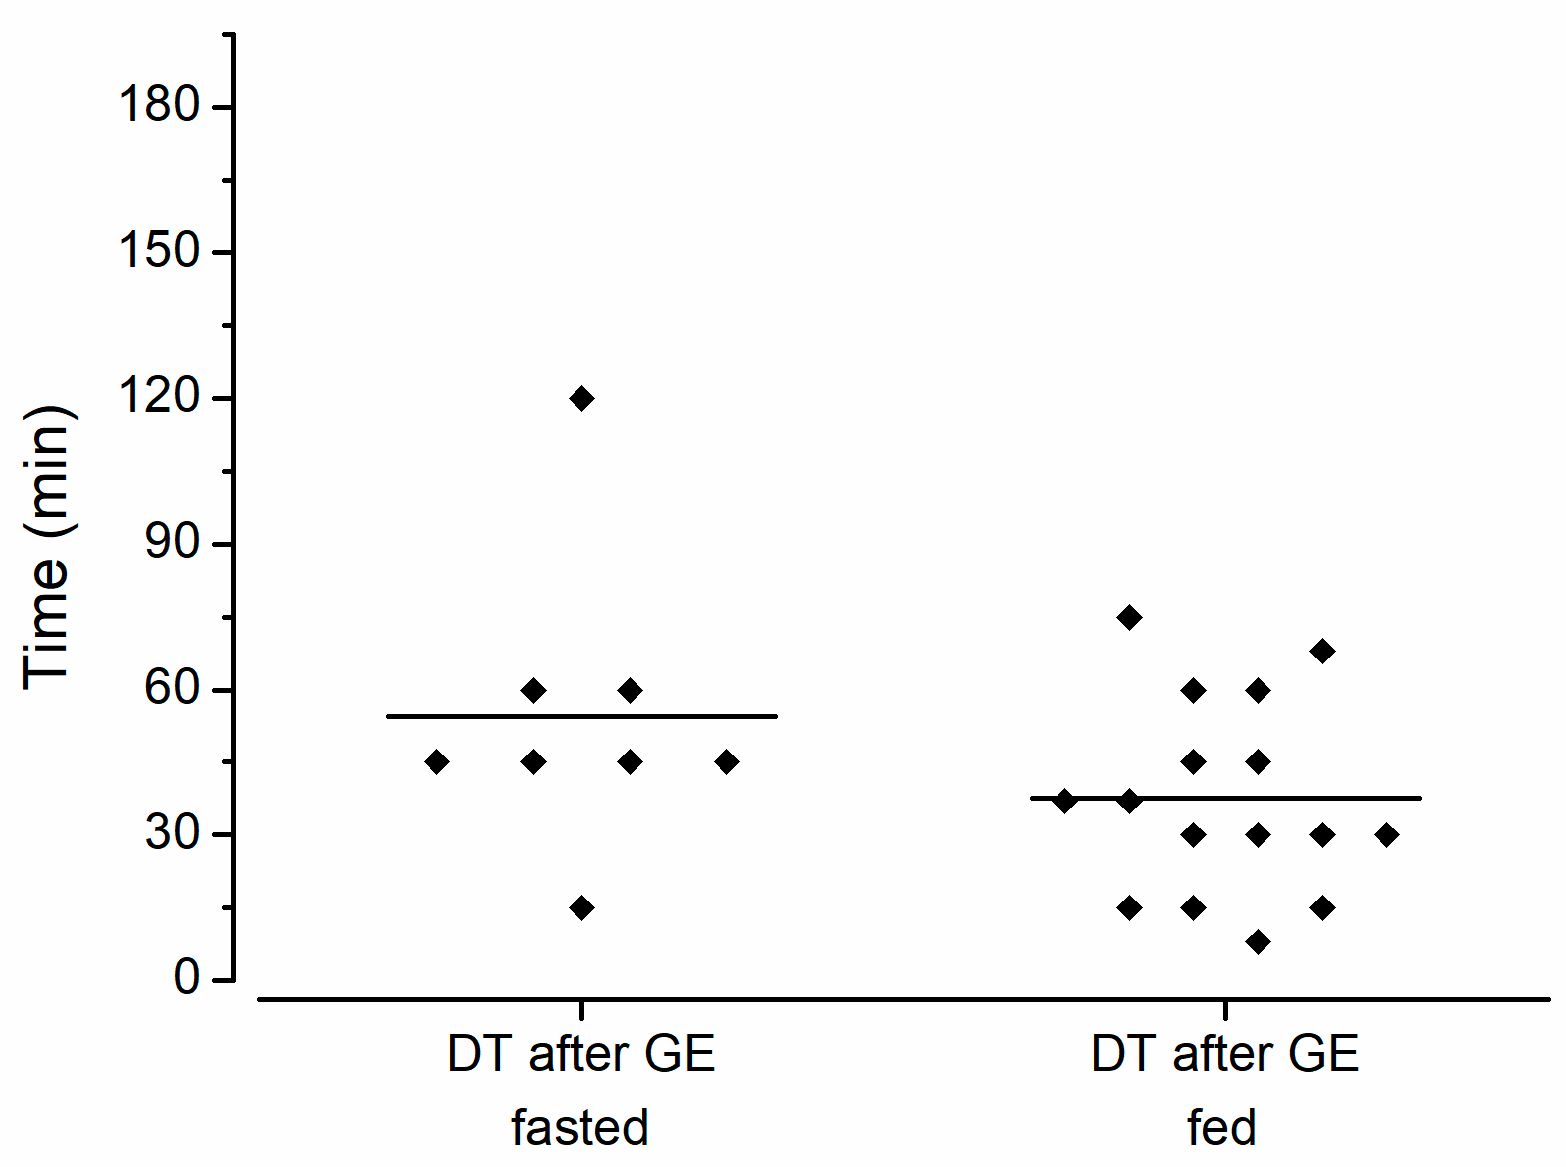

2.3. Experimental Design

3. Results and Discussion